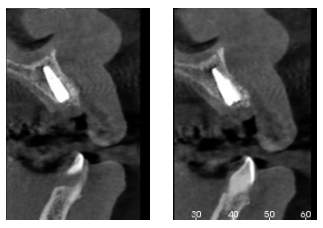

En la exploración radiográfica mediante radiografía panorámica se apreciaron los molares inferiores mesializados por la ausencia de los primeros molares inferiores (Figura 4A). En el escáner de haz cónico se evaluó el nivel de inserción del incisivo lateral superior izquierdo (Figura 4B).

verticales en zonas de molares. (B) Escáner de haz cónico, donde se aprecia el soporte óseo reducido del incisivo lateral

superior izquierdo.

Se colocó el injerto entre la superficie vestibular del implante, y la cortical vestibular, para cubrir el injerto con una esponja de fibrina (Gelatamp®) y dar dos puntos simples de sutura con poliamida no absorbible de 4/0 (Supramid®), realizando una radiografía periapical en el post-operatorio inmediato, para verificar la colocación adecuada del implante y del material de injerto (Figura 7). Así mismo, y con el objetivo de valorar el mantenimiento de la cortical vestibular se realizó un escáner de haz cónico realizado en el post-operatorio inmediato (Figura 8).

Sin embargo, para la colocación correcta de estos implantes inmediatos post-extracción en zonas anteriores, es importante que el implante se coloque a nivel del cíngulo de los dientes adyacentes, para que la prótesis tenga una buena vía de inserción y la restauración pueda realizarse de manera correcta22. Además, se recomienda tener 3-5 mm de disponibilidad ósea apical para asegurar la estabilidad primaria del implante25, tal y como se observa en el escáner realizado en este caso clínico. La estabilidad primaria del implante es una condición esencial de la que dependerá la realización o no de una provisionalización inmediata. Este anclaje exclusivamente apical y palatino hace necesario en la mayoría de las ocasiones la utilización de materiales de injerto22.